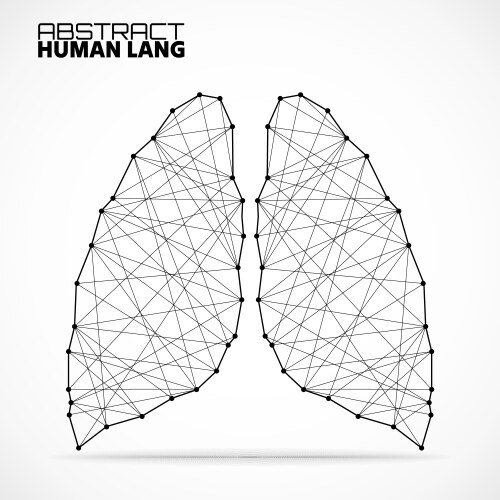

- Image ID

- 20721374

- Color Mode

- RGB

- Artist

- vladystock

- Lungs

- Abstract

- Lung

- Organ

- Human

- Chest

- Contour

- Creative

- Cybernetic

- Design

- Internet

- Matrix

- Shape

- Symbol

- Technology

- Connection

- Network

- System